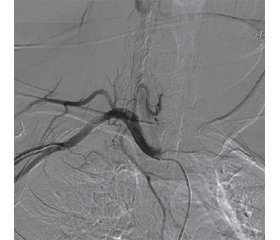

Імплантовані центральні порт-системи для в/в введення ліків широко використовуються в онкологічних хворих, які потребують тривалого доступу, проведення специфічного хіміотерапевтичного лікування та парентерального харчування. Встановлення центральних порт-систем вирішує проблему венозного доступу, але, на жаль, може призводити до ускладнень, у тому числі серйозних і необоротних. Наводимо клінічний випадок пацієнтки, 49 років, з онкологічною патологією, якій з метою проведення спеціалізованого лікування було імплантовано порт-систему для в/в терапії. Помилкове або недіагностоване розташування порт-системи у підключичній артерії та проведення сеансів неоад’ювантної поліхіміотерапії призвело до мієломаляції спинного мозку з подальшим розвитком мієлорадикулопатії, появи і розвитку стійких неврологічних порушень. Після радіологічної діагностики і верифікації цього ускладнення було проведено черезшкірну транслюмінальну балонну ангіопластику зі стентуванням одиничним стентом та видаленням центральної порт-системи. У цьому повідомленні описані ускладнення встановлення центральних порт-систем та детально розглянуто клінічний випадок ускладнення і методи його усунення при неправильній імплантації порт-системи в артерію.

Implanted central vascular access devices for intravenous administration of drugs are widely used in cancer patients who require long-term access, specific chemotherapy and parenteral nutrition. Installation of central vascular access devices solves the problem of venous access, but, unfortunately, it can lead to complications, including serious and irreversible ones. Here is a clinical case of cancer in a 49-year-old female patient who was implanted with a vascular access device for intravenous therapy. The incorrect and undiagnosed insertion of the vascular access device in the subclavian artery and also neoadjuvant polychemotherapy sessions led to myelomalacia with the subsequent development of myeloradiculopathy, the emergence and development of persistent neurological disorders. After radiological diagnosis and verification of this complication, percutaneous transluminal angioplasty with single stenting and removal of the central vascular access device was performed. The article presents complications with the insertion of central vascular access devices and discusses in detail a clinical case of complication and methods for its solution when this device is incorrectly implanted in the artery.